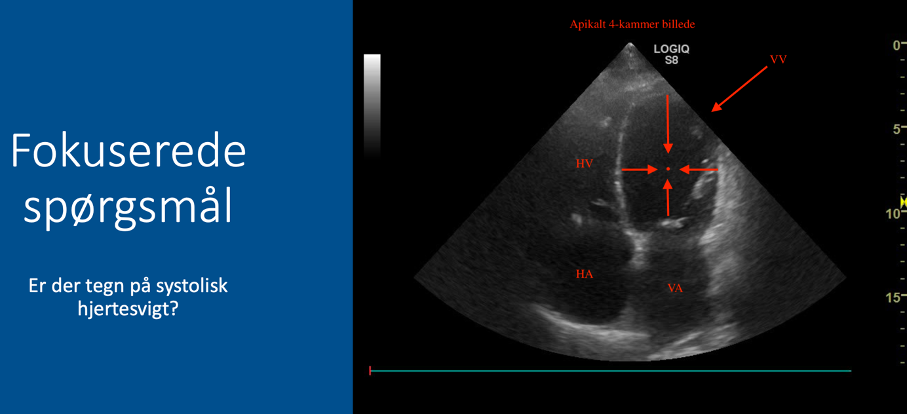

Fokuserede spørgsmål (FHUS):

* Tegn på systolisk hjertesvigt: ja/nej?

Kommer vægstrukturerne (hjertets vægge) mod midten i systolen?

* Hvis JA (væggene bevæger sig mod midten): IKKE tegn på systolisk hjertesvigt

* Hvis NEJ (væggene bevæger sig ikke ind mod midten, eller bevægelsen er sløv): tegn på systolisk hjertesvigt / nedsat EF (ejektionsfraktion)